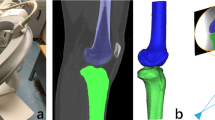

To simulate an anatomical single-bundle ACL reconstruction using the TP technique, the femoral tunnel of 10 mm diameter was created in 135° flexion model from the low far anteromedial portal which was previously marked with a coin during CT scanning (TP group). The same knee models were then drilled with the modified TT technique (TT group) using the same diameter at 90° of flexion separately (Fig. 1).

Computational simulation of femoral tunnel drilling. The femoral tunnel of 10 mm diameter was created in 135° flexion model from the low far anteromedial portal which was previously marked with a coin during CT scanning (TP group, A). The same knee models were then drilled through the modified TT technique (modified TT group, B) with the same diameter at 90° of flexion separately. TP: trans-portal, TT: trans-tibial